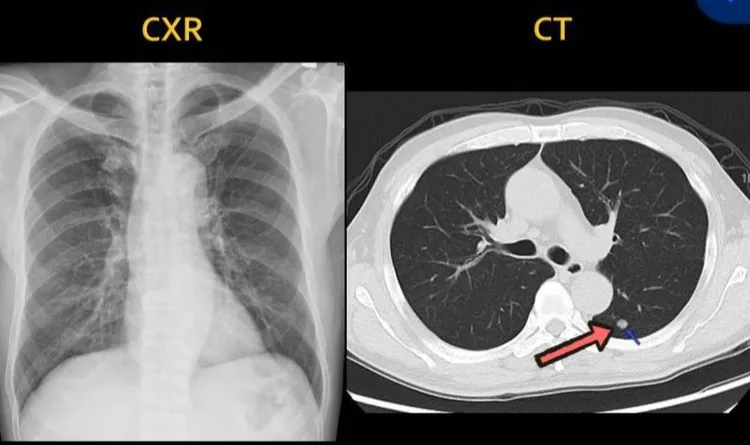

張先生X光片正常,斷層片有一顆肺結節。阮綜合提供

腫瘤大到1分以上才會被X光偵測到,低劑量電腦斷層可以偵測3~4mm大小的肺結節,在斷層偵測到的越小,越屬於早期範圍,治療上簡單安全又可能根治。反過來,X光檢查偵測不到1公分以下的腫瘤,若病灶位置在不易判讀的死角,會造成診斷治療延遲,延遲3至5年後,原本1公分可能長到7公分以上,甚至是第四期肋膜轉移或遠端轉移,晚期惡化的腫瘤,通常難以回天。